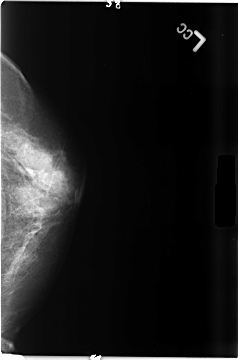

B_3480_1.LEFT_CC

LEFT_CC LINES 4672 PIXELS_PER_LINE 3088 BITS_PER_PIXEL 12 RESOLUTION 50 NON_OVERLAY